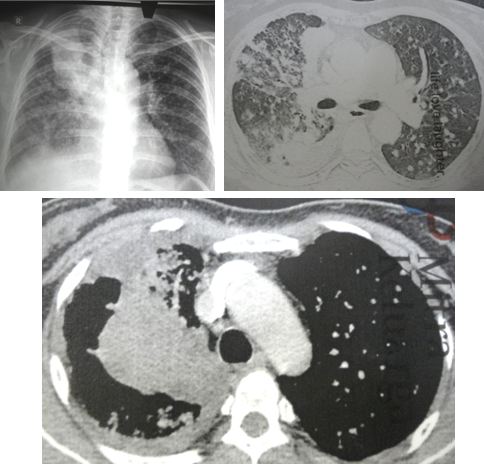

I had a chance to talk to his doctor who told me my brother had anaplastic thyroid cancer. In addition, there were extensive metastases in his lungs and liver.  Without doubt – by just looking at the CT scan images (below) – I knew that his days were numbered. No treatment would be able to save him.